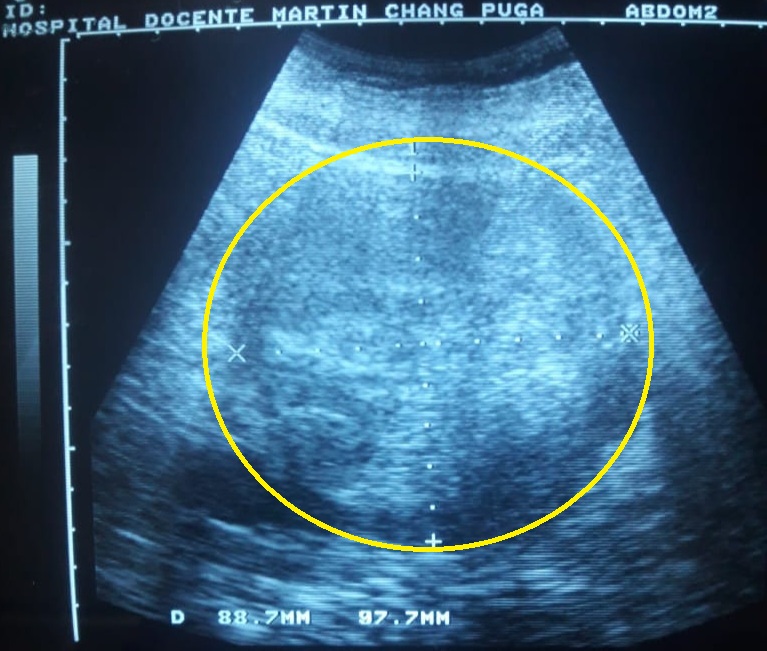

Estas características correspondían a una neoplasia sólida (aquística), sin hidronefrosis, ni invasión vascular aparente (Fig. 2).

Fig. 2 - Ultrasonido abdominal. El círculo amarillo delimita la imagen del hipernefroma.